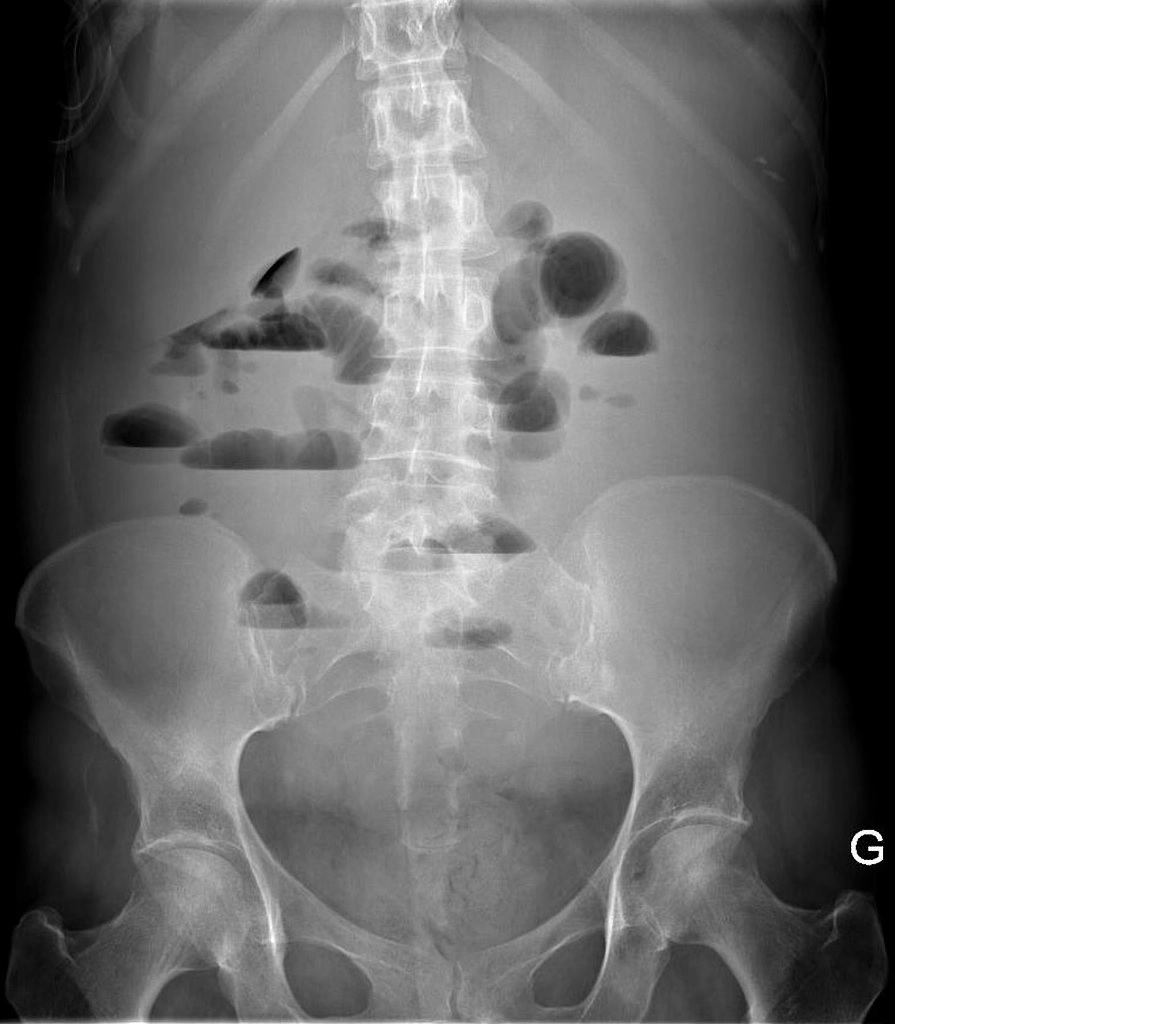

Хворий 23 років, доставлений бригадою ШМД зі скаргами на переймоподібний біль біля пупка, нудоту, блювання. З анамнезу захворювання відомо, що захворів гостро, раптово після переїдання. З анамнеза життя - періодично після порушення дієти відмічає біль у животі, схильний до закрепів. Прооперован у віці 2 років з причини хвороби Гіршпрунга. При огляді: у свідомості, положення вимушене на спині. Шкіра бліда, суха. Над легенями аускультативно жорстке дихання,  ЧДР - 20 за хв. Пульс 100 за хв. АТ 110/70 мм рт ст. Живіт дещо асиметричний за рахунок мезогастрія, де біля післяопераційного рубця пальпуються болючі, дилятовані петлі кишечника. Перитоніальні симптоми негативні. Симптоми Шланге позитивний. Аускультативно перистальтика різко ослаблена. Відмічається затримка відходження газів, стілець був вранці. Діурез знижений.

При ректальному дослідження: ампула прямої кишки пуста.

Клінічний аналіз крові: Нв - 120 г/л; Л - 11,5 Г/л

Оглядова рентгенографія органів черевної порожнини:

Який вид кишкової непрохідності має місце у пацієнта?